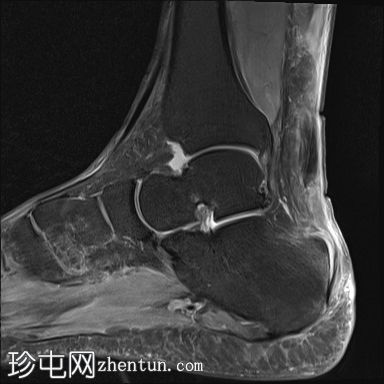

矢状位

PD脂肪抑制

跟腱完全撕裂,累及跟骨附着点,撕裂纤维近端回缩约38mm。回缩的肌腱明显肌腱病样改变和水肿。回缩肌腱下缘可见少量钙化碎片。

跟骨后侧可见骨髓水肿。

跟骨后侧可见皮质不规则,可能为肌腱附着点病变。

可见一小骨背侧骨刺。

可见明显的足底跟骨骨刺,足底筋膜增厚,可能为足底筋膜炎。

本病例显示跟腱近乎完全撕裂,累及跟骨附着点,撕裂纤维近端回缩。需行手术修复。放射科医生应注意撕裂部位和回缩程度。